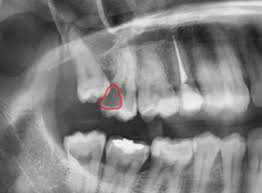

Der eine Nerv ist der Nervus alveolaris inferior der unterste Ast des Trigeminus-Nervs. Hatte ich noch nie eine Spritze im Mund. Weisheitszahn und zyste nerv nah - risiko.

Der Arzt hat das unterste Stück der Wurzel stehen gelassen da es etwas verwachsen sei und zu nah am Nerv. Mir wurde am Mittwoch 214. Dieser entscheidet ob eine operative Entfernung des Zahnes notwendig ist.

Häufig verläuft ein Nerv entweder durch die Wurzeln oder am Zahn entlang. Und bei nicht wenigen war es der fall dass der eingriff nah am nerv vorgenommen wurde das risiko also da war. Bevor ich meinen körper über jahre mit schmerzmitteln schädige und schmerzen leide würde ich mich diesem eingriff unterziehen.